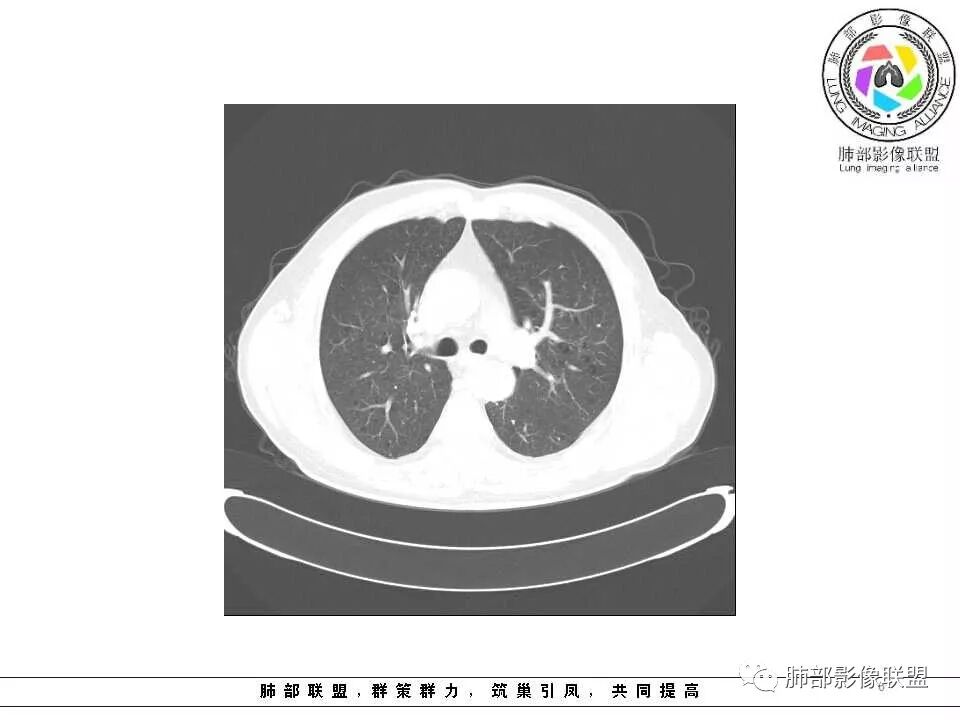

影像学特点:肺气肿背景下在大概一年的时间里出现了一个光滑的小结节,因为图像给的不是太薄,与支气管的关系判断不清,从结节周围出现斑片状炎症来判断,应该考虑结节位于支气管内,周围是阻塞性炎症,这样比较容易解释咯血

左肺上叶结节边缘清晰尚规整伴子灶及炎性病变 临床咯血无发热  早期肺癌?

老年男性,左肺舌段见多个小结节灶及斑片状高密度灶、磨玻璃影,结节灶边界清晰,光滑,无明显分叶,密度均匀,周围病灶密度不均,一年内生长,考虑恶性肿瘤并阻塞性肺炎出血,小细胞可能大。

老年男性,肺气肿背景,左肺上叶舌段结节明显增大,边缘膨隆,有磨玻璃结节,与血管联系紧密,周围可见条片影,首先考虑恶性肿瘤,鳞癌伴阻塞性炎症,鉴别炎性

老年男性,以咯血为主要表现,CT左肺舌段结节影,实性,边缘清楚锐利,部分膨胀,周围磨玻璃结节及树芽征,周围有空气潴留,首先考虑占位,鉴别结核。

左肺上叶舌段见前后两个小结节,边缘清晰,无分叶毛刺,前方小结节见小气管穿行,临近血管纹理无牵拉,结节下方层面见条片状密度增高影,局部纹理增强,边缘模糊,内见气管影,上肺上叶见多个小透光区,纵膈内见增大小淋巴结影,考虑1·良性改变,炎性可能,2·肺气肿。病变短期变化明显,肿瘤不考虑,结节与舌段肺炎关系不大